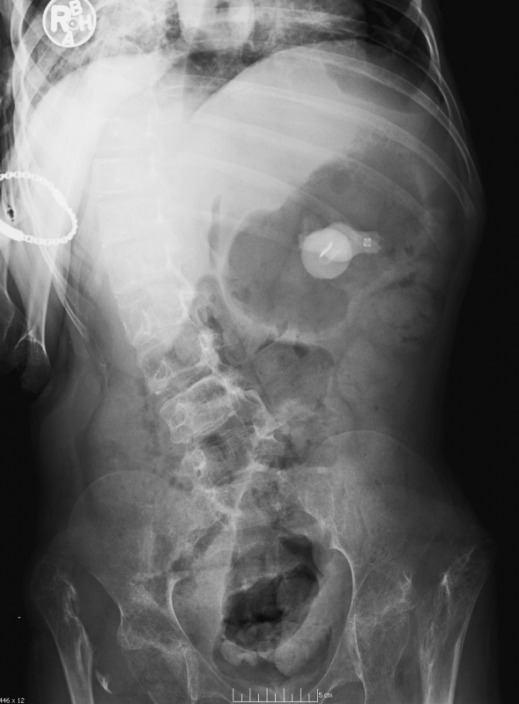

13 year old male.

1.  What are your key findings?

2.  Do you have a differential diagnosis?

Click here for the case of the month discussion.